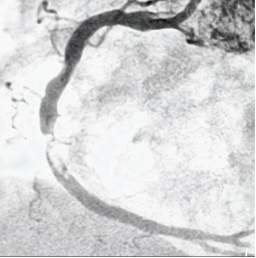

医生在接诊。